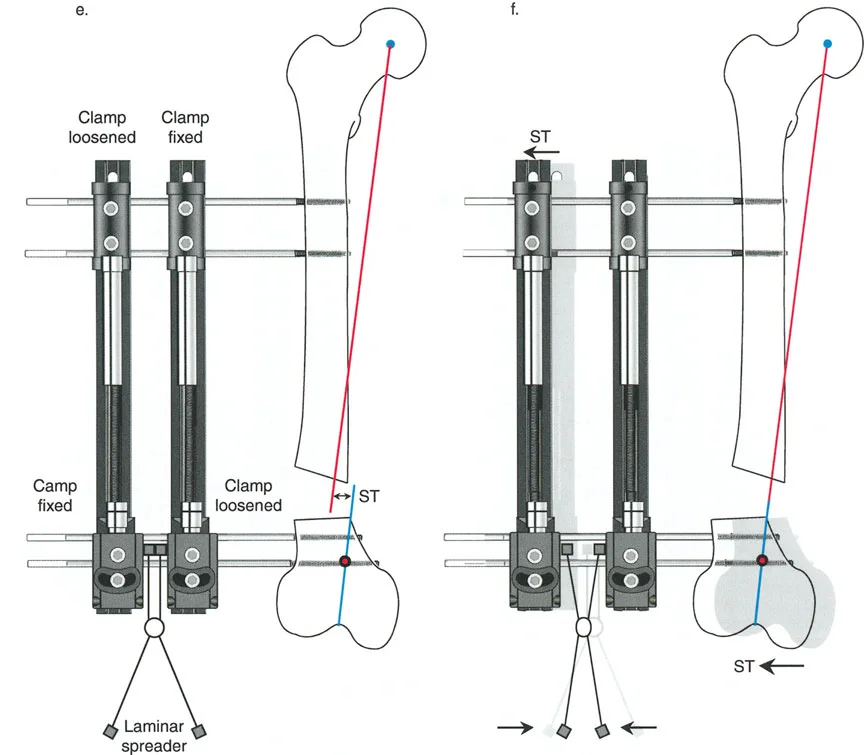

قيود الأسلاك والدبابيس في القاعدة 2

لتحقيق هذه الترجمة الضرورية والمقصودة بسلاسة باستخدام إطار دائري كامل الأسلاك، يلزم استخدام أسلاك الزيتون المعاكسة (counter-opposed olive wires). تعمل أسلاك الزيتون كقوى سحب ديناميكية، تسحب قطعة العظم على طول الحلقة أثناء فتح المفصلات. بدون أسلاك الزيتون، سيبقى العظم ثابتًا بينما تتحرك الحلقة عبر الأنسجة الرخوة، مما يسبب نخرًا شديدًا في الجلد.

على العكس من ذلك، إذا تم استخدام دبابيس نصفية (مسامير شانز)، فإنها تقيد العظم بطبيعتها بالحلقة. نظرًا لأن الدبابيس النصفية هي أذرع صلبة (مثبتة من طرف واحد بالحلقة ومغروسة في العظم من الطرف الآخر)، فإنها لا تسمح للعظم بالانزلاق على طول محور السلك. هذا يجعل أسلاك الزيتون غير ضرورية للترجمة في منشآت الدبابيس النصفية، ولكنه يتطلب من الجراح التأكد من أن الدبابيس النصفية قوية بما يكفي (عادةً دبابيس بقطر 5 مم أو 6 مم مطلية بهيدروكسي أباتيت) لتحمل لحظات الانحناء الناتجة عن الترجمة.

نصائح جراحية للمنشآت القريبة من المفصل

| المبدأ | التطبيق السريري | تحذير / خطأ محتمل |

|---|---|---|

| التحقق من CORA | دائمًا تحقق من CORA الحقيقي في الأشعة السينية الطويلة للطرفين قبل بناء المفصلة. | الاعتماد على الأشعة السينية القصيرة للركبة سيؤدي إلى CORA غير دقيق وبالتالي سوء محاذاة. |

| ACA العمودي | تأكد من أن محور المفصلة (ACA) عمودي تمامًا على مستوى التشوه. | محور ACA مائل سيحدث تشوهًا ثانويًا غير مرغوب فيه (مثل تصحيح التقوس ولكن إحداث الانحناء الأمامي). |

| تخليص الأنسجة الرخوة | عند استخدام قاعدة قطع العظم 2، احسب الترجمة المتوقعة وتأكد من أن الأنسجة الرخوة يمكن أن تستوعبها. | عدم مراعاة الترجمة يمكن أن يتسبب في اصطدام العظم بالجلد، مما يؤدي إلى النخر. |

| تقابل الأسلاك | استخدم ما لا يقل عن سلكين زيتون متقابلين لكل قطعة إذا كنت تتجنب الدبابيس النصفية. | الأسلاك الزيتون الفردية ستسبب قصًا ودورانًا غير مرغوب فيه حول محور السلك. |